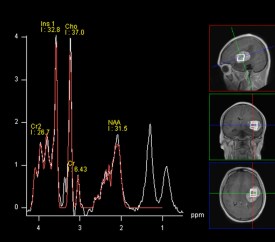

IRM fonctionnelle langage de connaître ses relations précises avec les régions fonctionnelles : tenseur de diffusion, IRM fonctionnelle

- et de former des hypothèses sur sa nature (séquences de diffusion, spectro-IRM) ; l’imagerie seule ne permet cependant pas de se passer d’une certitude histo-pathologique.